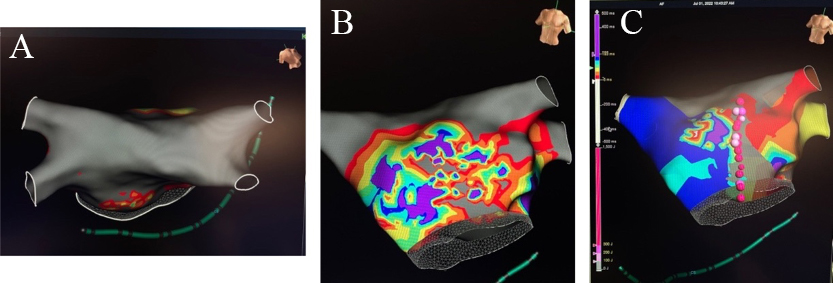

The completion of the HTT Maze approach is performed via an endocardial catheter ablation in a similar fashion to the Convergent hybrid approach. Endocardial mapping is performed to identify gap areas in the epicardial lesions that require additional endocardial ablation and/or to identify the mitral and tricuspid isthmus for additional ablation (Fig. 8). With the addition of these endocardial lesions, the complete hybrid approach lesion set closely approaches the fundamental Cox-Maze III/IV. The most common reported endocardial energy applied is radiofrequency, however cryoballoon has also been utilized [23].

Fig. 8.

Fig. 8.Completion of the Hybrid TT Maze. (A) Endocardial map after 1st stage Totally Thoracoscopic ablation with complete isolation of bilateral pulmonary veins and posterior wall with (B) partial epicardial anterior mitral line and (C) endocardial anterior mitral line completion.